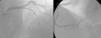

A coronariografia (Figura 2) revelou doença coronária de 2 vasos (lesão de 75% no segmento médio da descendente anterior e lesão de 90% na origem da descendente posterior). O estudo hemodinâmico determinou um gradiente transvalvular aórtico de 97mmHg.